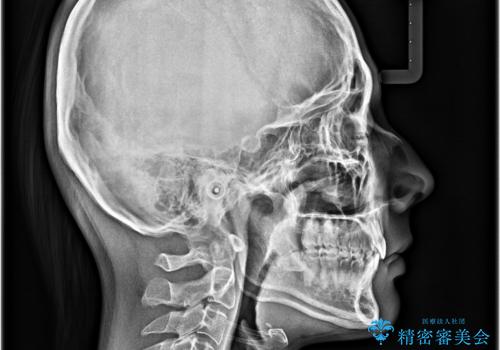

下顎前歯が全て隠れてしまうほどの深い咬合で、左右の奥歯は1歯対1歯で咬み合う状態でした。

前方に移動している上顎臼歯を補助装置にて遠心移動させることで1歯対2歯の臼歯咬合を目指し、同時に深い咬合を改善していくこととしました。

このような咬み合わせの場合、治療期間は2年以上がかかることが一般的で、3年程度かかることもありえるケースです。

強く深い咬み合わせにより下顎装置は頻繁に脱離するため、治療期間が長くなりますが、予定通りに終了させることができました。